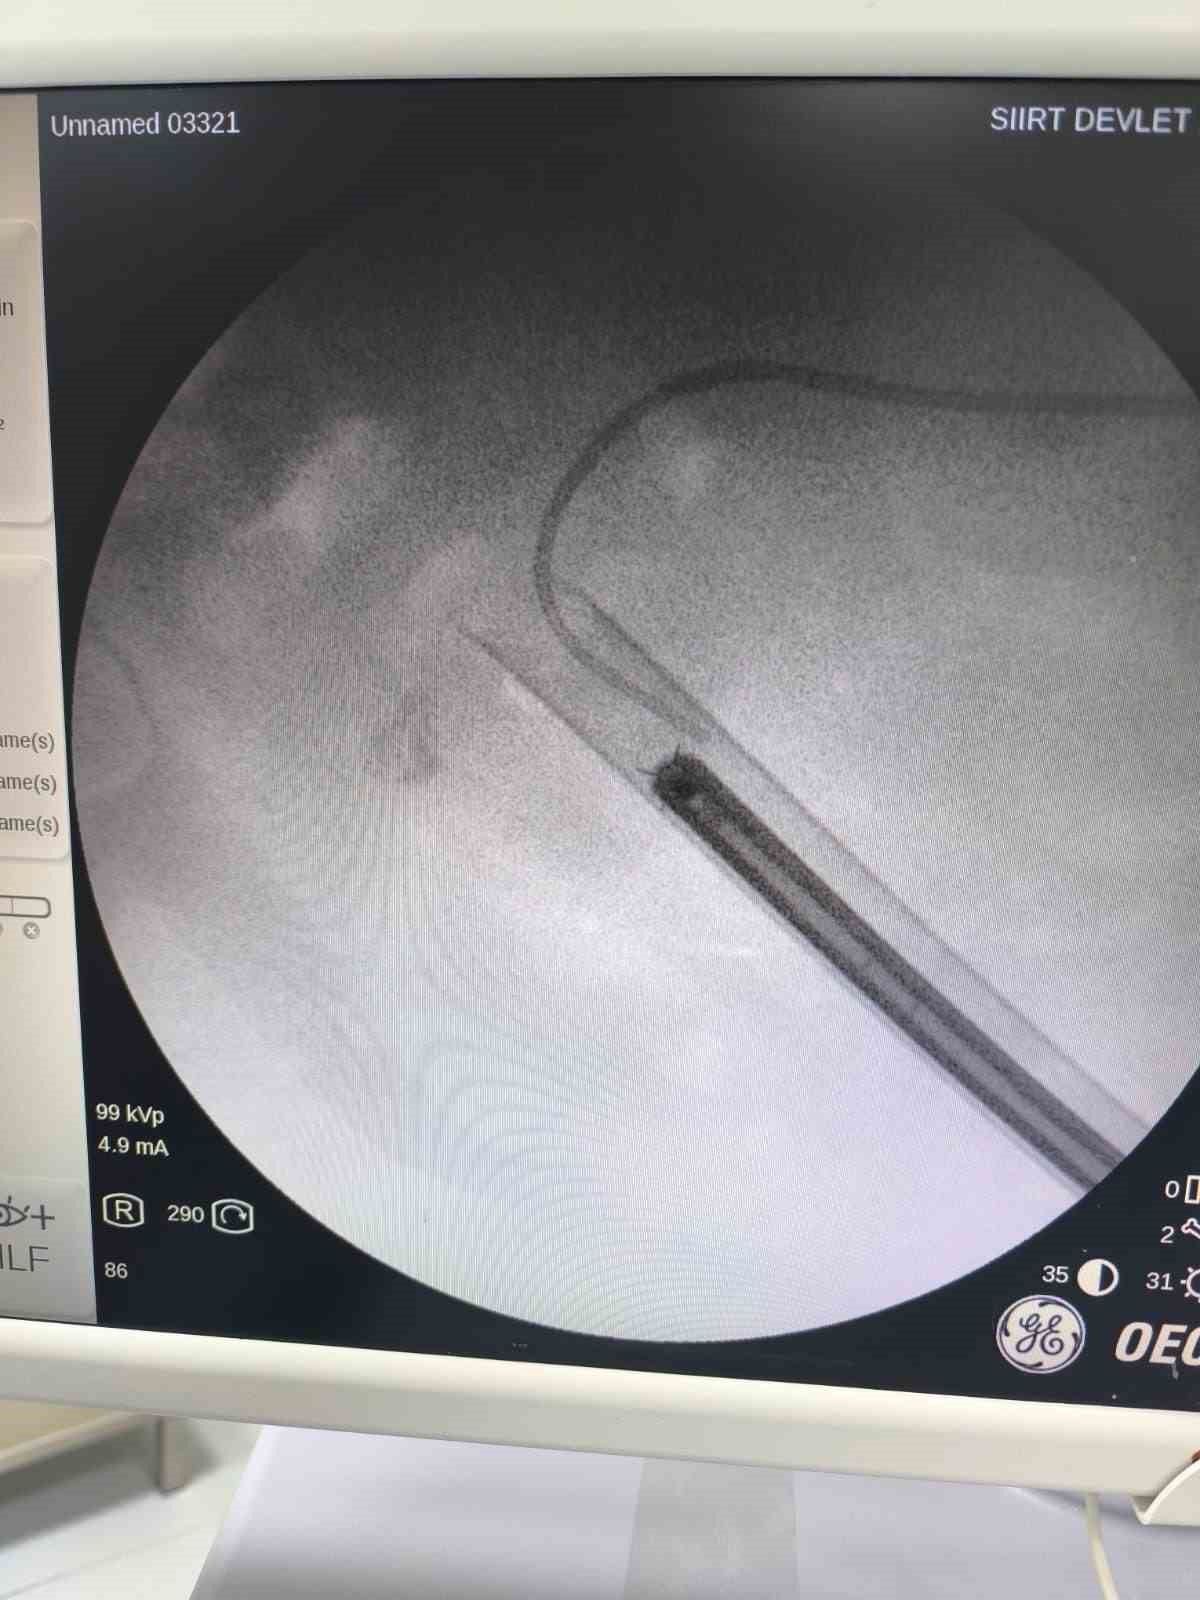

Siirt’te 34 yaşındaki Fatih Aslan, ateş, üşüme ve idrar yaparken yanma şikayetleriyle hastaneye başvurdu. Yapılan muayene ve testlerin ardından piyelonefrit (böbrek iltihabı) tanısı konuldu ve enfeksiyon tedavisi tamamlandı. Üroloji uzmanı doktor Miraç Ataman, gerçekleştirilen operasyon, hem tıbbi açıdan hem de toplumsal sağlık açısından önemli bir başarı olduğunu söyledi. Ataman, "34 yaşındaki erkek hastamız, ateş, üşüme ve idrar yaparken yanma şikayetleri ile acil servise başvurdu. Yapılan değerlendirme sonucunda piyelonefrit (böbrek iltihabı) tanısı konuldu ve yatış yapılarak enfeksiyon tedavisi başarıyla tamamlandı. Tanı sürecinde yapılan Bilgisayarlı Tomografi (BT) görüntülemesinde böbreğin tamamını kaplayan, sert yapıda(950-1450 HU), literatürde staghorn olarak adlandırılan ve halk arasında ‘ geyik boynuzu taşı ’ diye bilinen büyük taş saptandı. Staghorn taşlar böbreğin tüm boşluklarını doldurup, tekrarlayan enfeksiyonlara ve uzun vadede böbrek fonksiyon kaybına yol açabildiğinden tedavisi hayati önem taşımaktadır. Biz de bu vakamızda, Perkütan Nefrolitotomi (PCNL) yöntemiyle böbreğe küçük bir cilt kesisi üzerinden girerek endoskopik cihazlarla taşları parçalayıp çıkardık. PCNL, özellikle çapı 2 cm’den büyük ve kompleks taşlarda altın standart kabul edilmektedir. Normalde staghorn taşların temizlenmesi uzun süren ve çoğu zaman birden fazla seans gerektiren zorlu bir süreçtir. Modern altyapısı sayesinde, ciltten tek giriş yolu açılarak yaklaşık 1,5 saatlik bir seansta böbreğin tüm taş yükü başarıyla temizlendi" dedi.

Hasta Fatih Aslan, hastaneye idrar ağrısıyla geldiğini belirterek, "Böbrekte ciddi bir taş olduğu ve bu taşla doktor ilgilendi Allah razı olsun. Böyle bir taşın en az 3 ameliyatla alınacağı söylenildi. Tek seansta hallolması epey mutlu etti" diye konuştu.